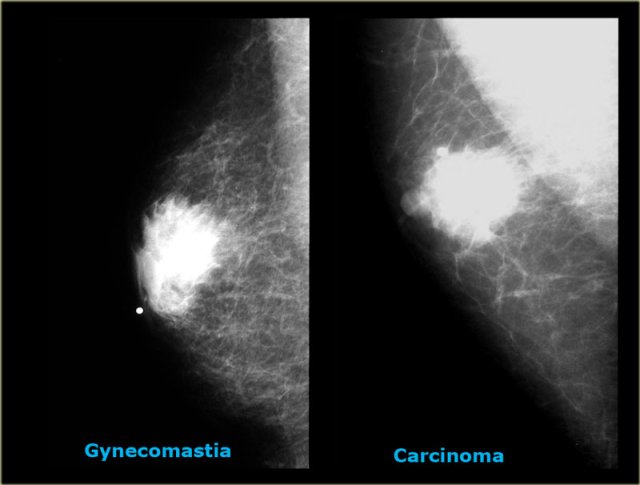

On the left two cases, that demonstrate, that it can be difficult to differentiate gynecomastia from carcinoma on a mammogram.

The carcinoma on the right is a little bit more encapsulated than the gynecomastia on the right.

In less than 10% of the cases a biopsy can be needed to make the differentiation.